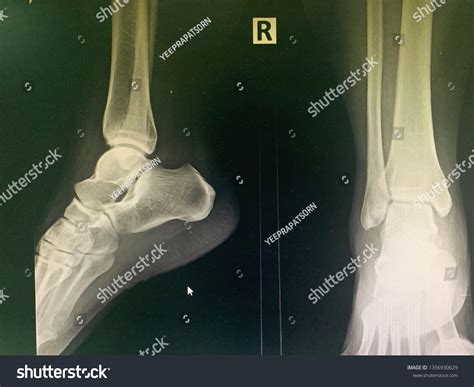

A Lateral Ankle Xray is a specific type of X-ray that provides a side view of the ankle. This view is particularly useful for assessing the alignment of the bones and identifying fractures or dislocations. The lateral view complements other views, such as the anteroposterior (AP) and mortise views, to give a comprehensive picture of the ankle's condition.

Interpreting a Lateral Ankle Xray requires a trained eye to identify key features and abnormalities. Some of the important aspects to look for include:

• Bone alignment: Ensuring that the bones are properly aligned and there are no signs of fractures or dislocations.

• Joint space: Assessing the width and uniformity of the joint space to detect any signs of arthritis or other joint issues.

• Soft tissue swelling: Identifying any swelling or inflammation around the ankle that may indicate an injury.

Radiologists and orthopedic specialists are trained to interpret these images and provide a detailed report of their findings. This report is then used to guide treatment decisions.

Common Findings on Lateral Ankle Xray

Some of the common findings on a Lateral Ankle Xray include:

• Fractures: Visible breaks in the bones, which may be simple or complex.

• Dislocations: Misalignment of the bones, often due to severe trauma.

• Osteoarthritis: Changes in the bone structure and joint space indicative of degenerative joint disease.

• Soft tissue swelling: Inflammation or edema around the ankle, which may be due to injury or infection.

These findings help healthcare professionals determine the appropriate course of treatment, which may range from conservative measures such as rest and immobilization to surgical intervention.